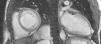

The diagnosis was confirmed in all patients by MRI on a 1.5-T Magnetom Symphony scanner (Siemens Medical Solutions) using Petersen et al.’s criterion: a ratio of end-diastolic thickness of non-compacted to compacted layers of >2.3.2

In our center we follow the criteria of Jenni et al., as they are the most commonly used. However, as pointed out by several authors,20,21 it can be difficult to obtain rigorous and reproducible measurements of the thickness of the compacted and noncompacted layers, and so all patients also underwent MRI to confirm the diagnosis. This technique, as well as showing good agreement with echocardiographic findings, also has superior spatial resolution that enables better visualization of the LV apex and lateral wall, which are often involved in noncompaction. We consider that images from MRI are particularly suitable for quantitative assessment, for which the standard criteria are those of Petersen et al., as used in this study (see Methods). In 2010, Jacquier et al. showed that measurement of trabeculated LV mass by MRI can be used in the diagnosis of LVNC. According to these authors, a value above 20% of the total mass of the LV has high sensitivity and specificity for the diagnosis of LVNC (Figures 1 and 2).22